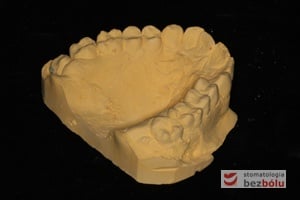

- Odlanie modelu protetycznego diagnostycznego.

- Wykonanie specjalistycznego modelu poprzez odcięcie wyrostka zębodołowego i separacje poszczególnych zębów, a następnie zespolenie za pomocą wosku modelowego.

- Wykonanie ostatecznego modelu gipsowego celem natłoczenia szyny, izolacja modelu.